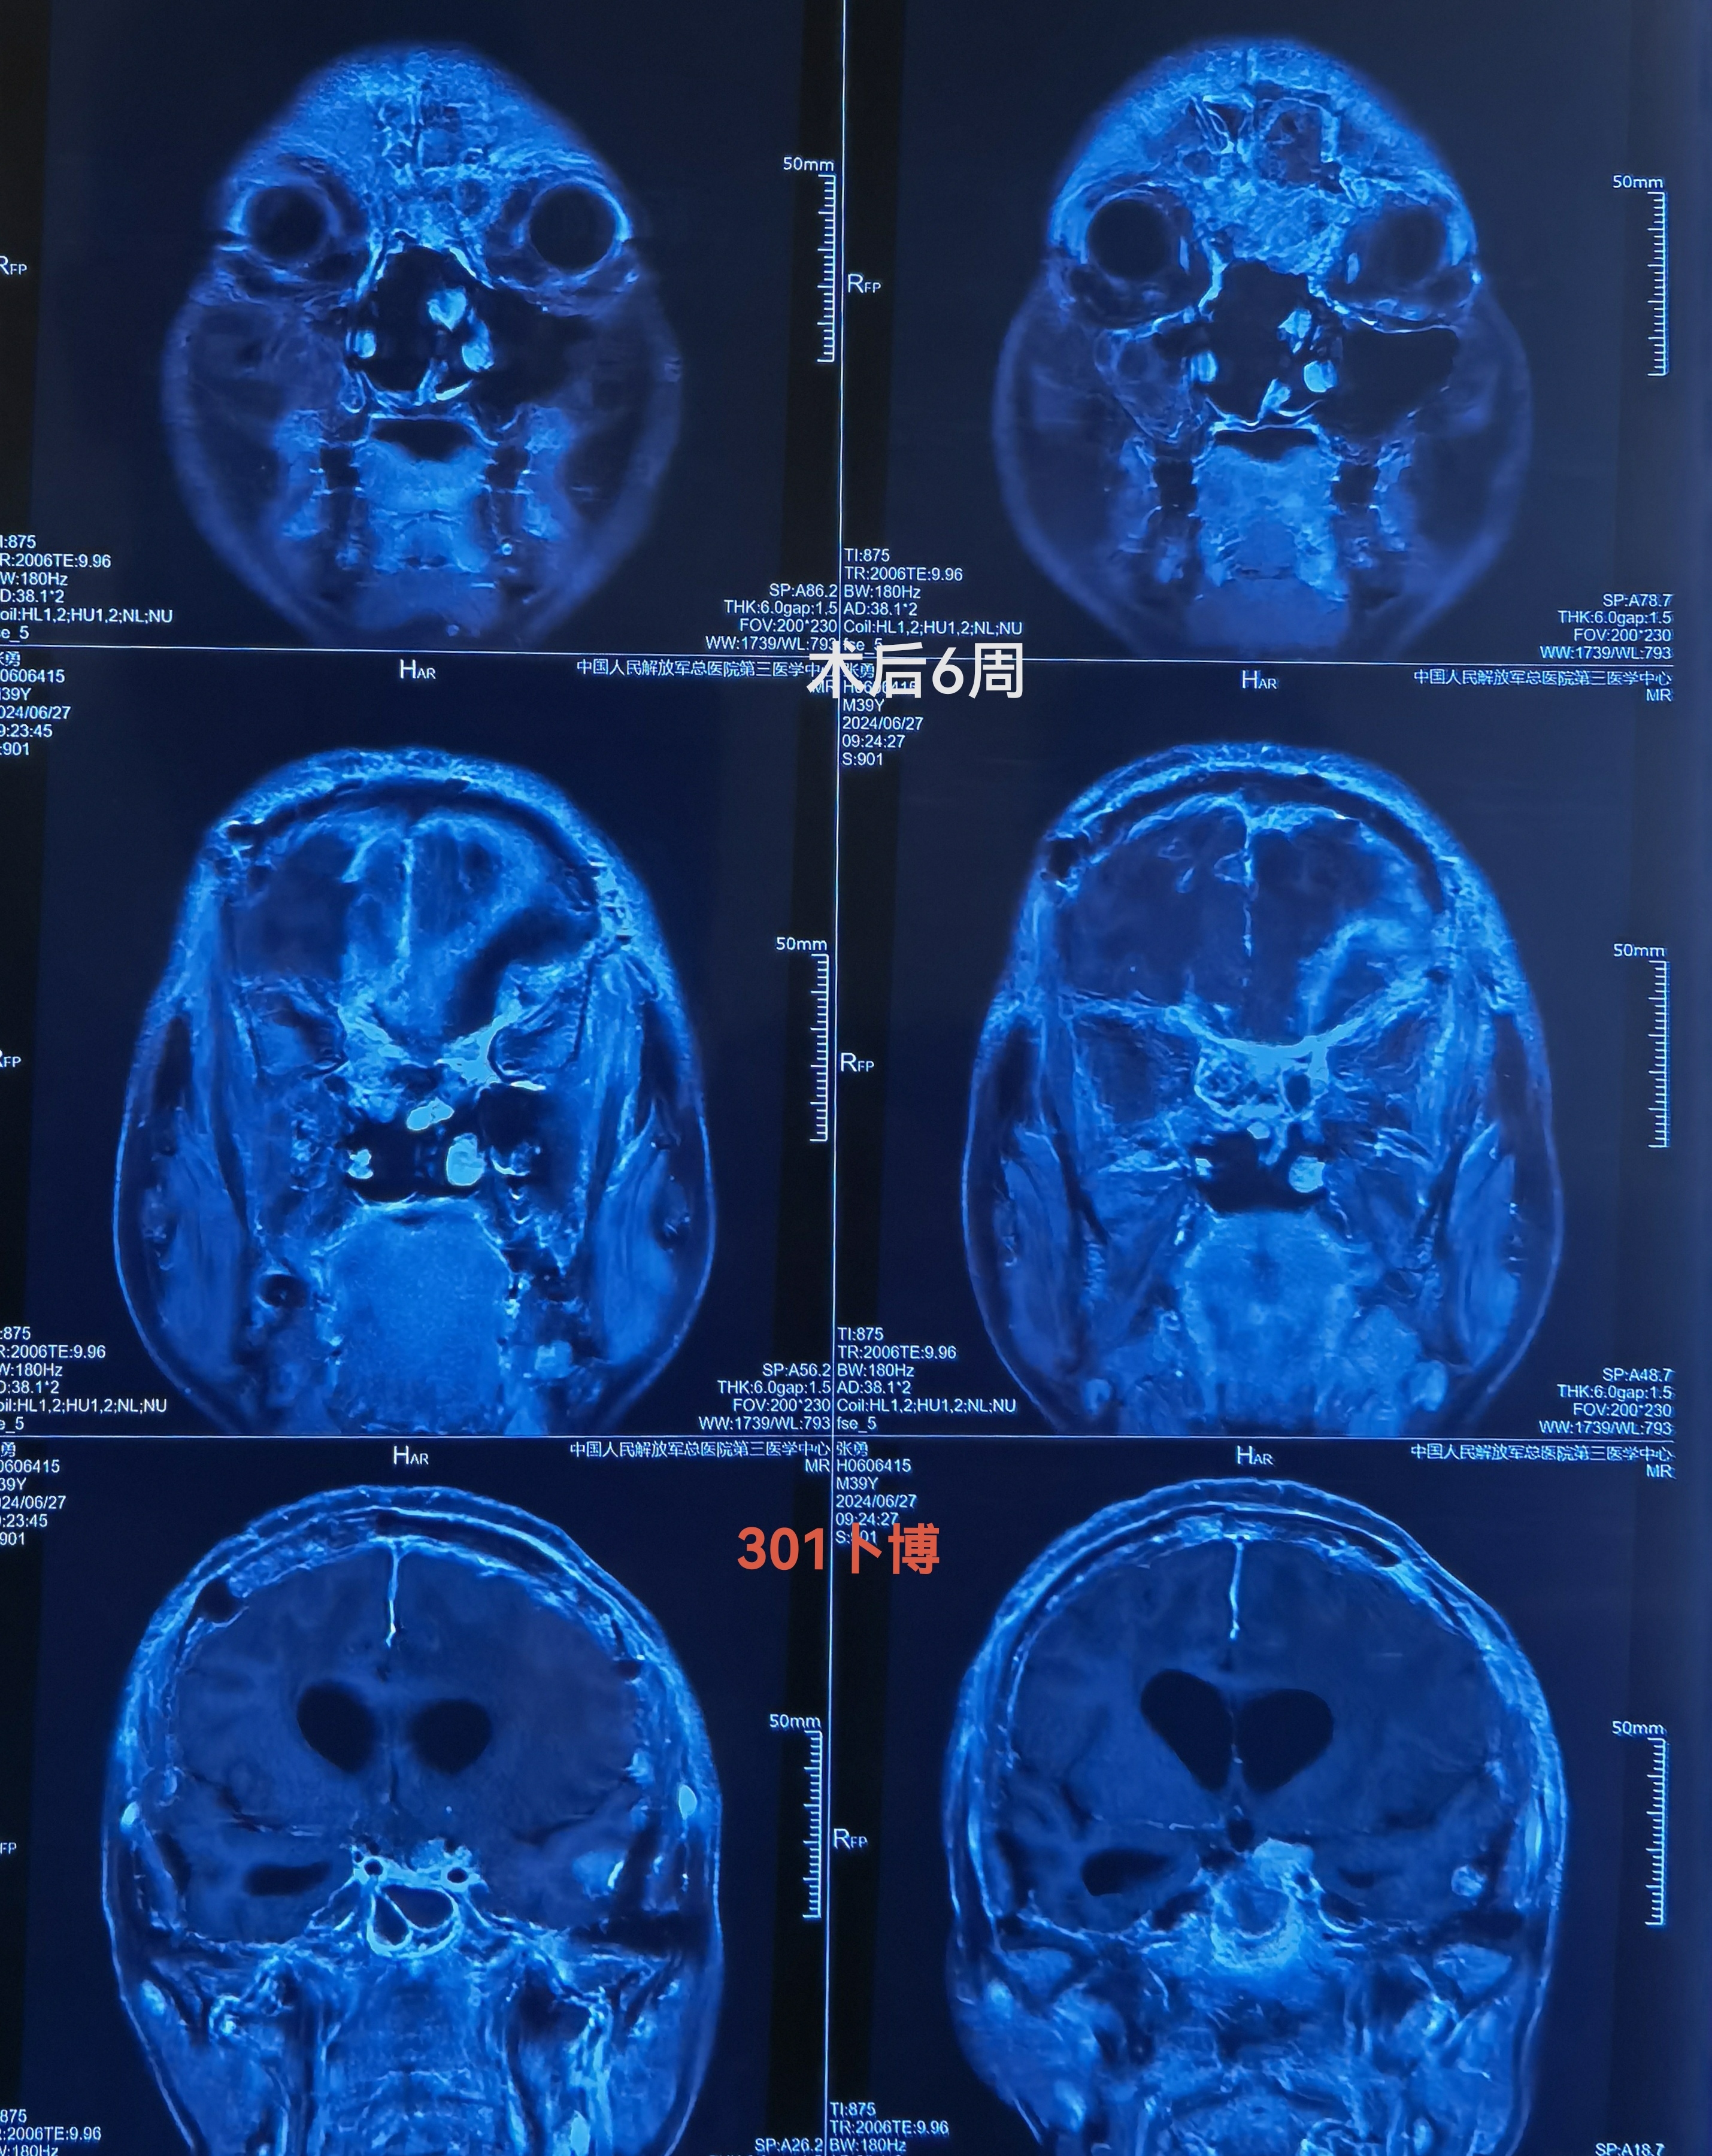

MRI可见肿瘤巨大,中鼻道以上,蝶窦筛窦及双侧额底均为肿瘤组织占据,向两侧到蝶骨嵴。肿瘤分叶状,可明显增强,核心区有坏死。后部可见粗大的静脉。双侧大脑前动脉位于肿瘤的后部。

枕大孔区种植转移,挤压脑干。已于6周前切除。